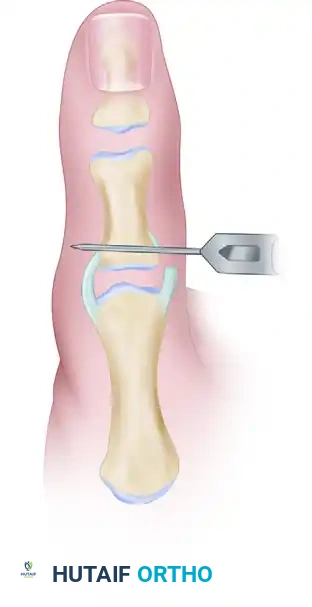

The Pull-Out Wire Technique

- To insert a pull-out wire, use a 0.035-inch or 0.045-inch Kirschner wire and drill a hole through the proximal end of the proximal phalanx, starting at the ulnar footprint and exiting on the radial cortex.

- Place a Bunnell or Krackow pull-out suture (using a non-absorbable or heavy absorbable suture, or a wire loop) through the avulsed, hemorrhagic end of the ligament.

- Pass the ends of the suture through the transosseous drill hole in the phalanx using a suture passer or a straight Keith needle.

- While holding the joint in slight flexion and applying a gentle ulnar-directed force to reduce the ligament to its footprint, tie the suture ends over a padded button on the radial side of the thumb.

- Pass the twisted pull-out wire loop through the skin near the incision before final closure to facilitate removal in the clinic setting.

- After identifying the site of avulsion and preparing the bone bed, drill two divergent holes beginning on the ulnar base and exiting on the radial base of the proximal phalanx using a 0.035-inch Kirschner wire.